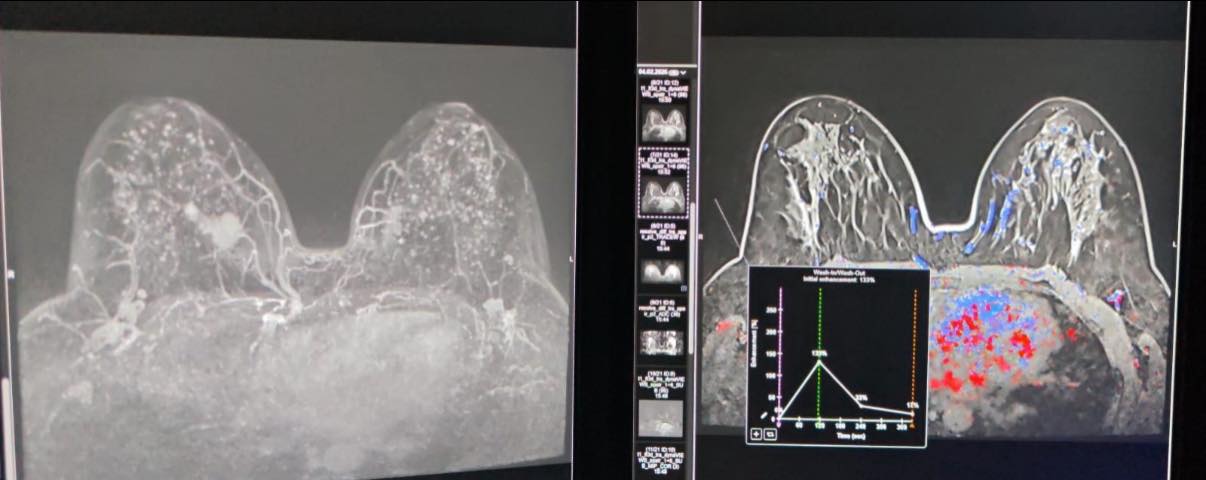

O pacientă de 39 de ani s-a prezentat inițial la mamografie pentru o anomalie palpatorie, iar investigația a evidențiat o leziune suspectă la sânul drept. Densitatea crescută a țesutului mamar a impus completarea investigațiilor cu un examen IRM, care a identificat o a doua leziune suspectă la celălalt sân. Decizia echipei medicale a fost de a biopsia ambele formațiuni.

Prima leziune a fost abordată cu succes sub ghidaj ecografic, în timp ce cea de-a doua a necesitat corelarea imaginilor IRM cu ecografia în timp real, pentru localizare precisă și biopsiere sigură. Procedura s-a realizat cu ajutorul noului echograf de ultimă generație, achiziționat prin proiectul „Îmbunătățirea Performanțelor de Diagnostic și Tratament al Patologiilor Tumorale prin Dotarea Spitalului Clinic Județean de Urgență ‘Sfântul Apostol Andrei’ Constanța cu Echipamente de Ultimă Generație”, cofinanțat din Fondul European de Dezvoltare Regională (FEDR) prin Programul Sănătate.

“Biopsia sub ghidaj IRM rămâne standardul de aur pentru leziunile detectabile exclusiv prin această metodă, dar tehnica de fuziune imagistică oferă o soluție valoroasă în cazurile dificile și crește precizia diagnosticului”, a declarat dr. Alexandru Gavrilă, medic radiolog, specialist în mamografie.